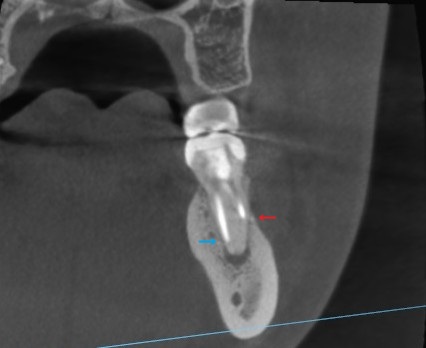

先ほどのCT写真で2つの根を1つずつ見ます。

まずはこちら、近心の歯根のを点線の断面で見てみます。

正面から見た歯の断面です。

青い矢印が長く根管に充填されていますが、歯の根には黒い影があります。

赤い矢印は根の横側へ、誤った方向に穿孔しています。

※穿孔(読み:せんこう)(英名:パーフォレーション)といって、本来の根管と違う方向に器具が進み、根管内に穴があいてしまっています。

間違った方向に歯を削り進めたため起こる医療ミスです。